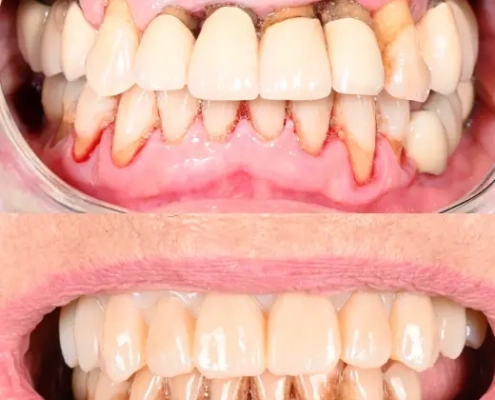

Dysfonction occlusale et esthétique avec inflammation gingivale, usure dentaire marquée et axes implantaires défavorables au maxillaire, compromettant une réhabilitation prothétique transvissée sans correction d’angulation.